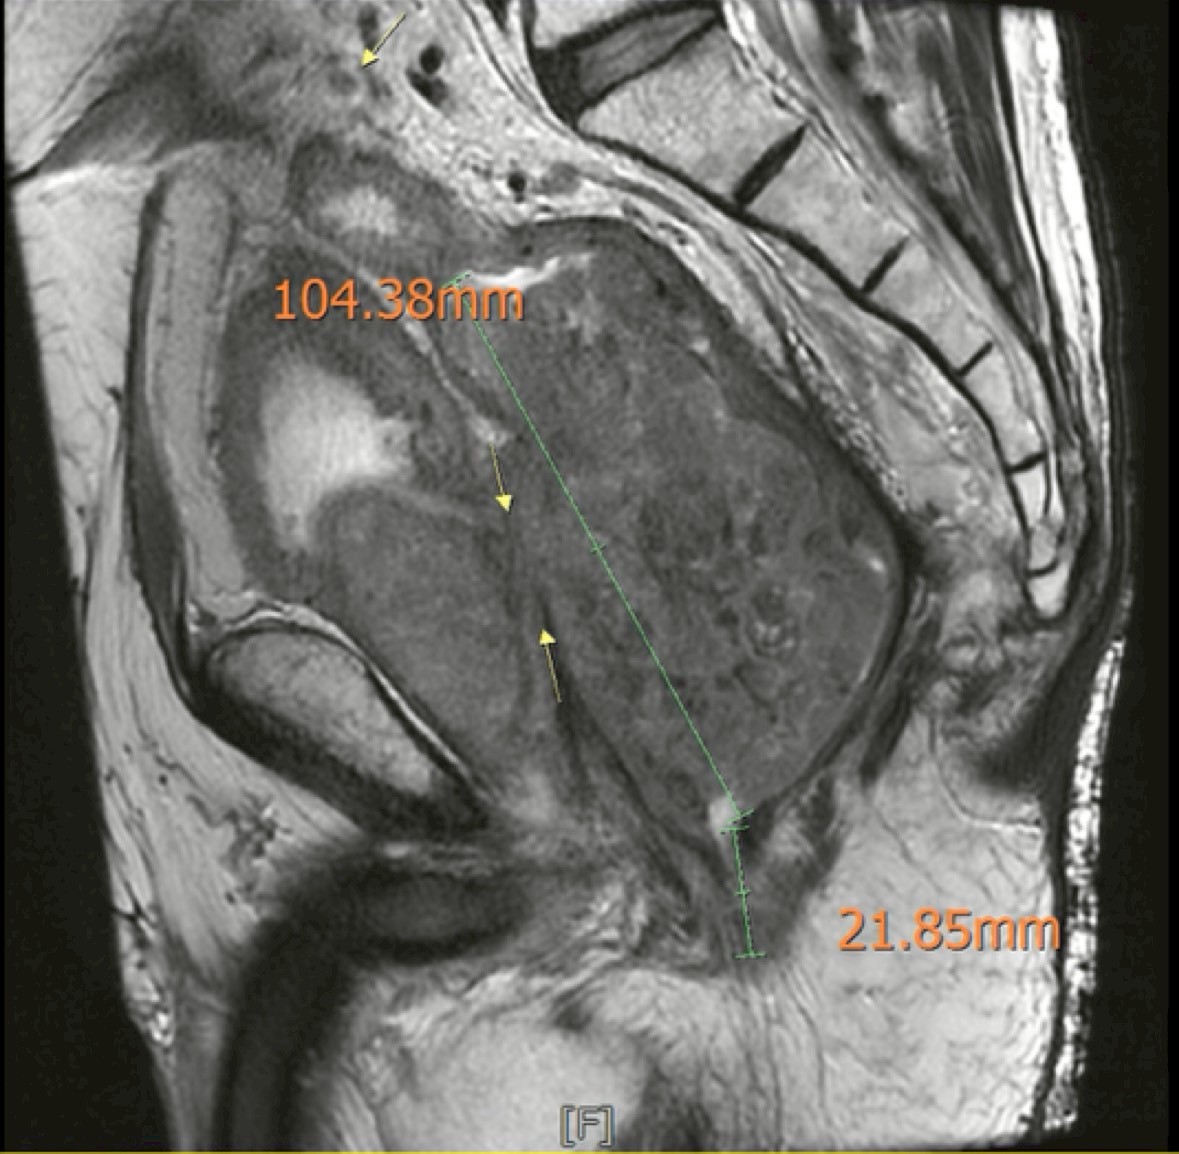

腫瘤大小核磁共振照片

61歲的王先生,大約一年前被診斷為巨大局部晚期直腸癌,腫瘤已經侵犯到泌尿系統。更嚴重的是,腫瘤破裂引發了會陰部壞死性筋膜炎,這是一種致命性很高的感染,當時的首要任務是保住性命。在經過緊急清創與感染治療後,王先生開始接受標準的新輔助放射線與化學治療,在放化療的過程中,腫瘤確實有反應,也有局部縮小。然而,在療程結束之後,王先生卻遲遲沒有接受手術治療,後續治療以口服化療與支持性療法為主,接下來的半年,王先生的生活品質並不好。由於腫瘤侵犯泌尿道,他開始出現反覆泌尿道感染、發燒、虛弱與營養不良的情況,身體狀況每況愈下。最後,因為反覆感染,他來到台中中國醫藥大學附設醫院找直腸外科黃晟瑋醫師求診。

在感染穩定之後,重新安排影像檢查,結果顯示:腫瘤處於穩定狀態,沒有遠端轉移,也沒有明顯惡化。這代表一件很重要的事情——腫瘤仍然有機會透過手術完整切除。

更重要的是,病理報告顯示腫瘤切除邊緣是乾淨的(R0 resection),代表腫瘤已被完整切除。目前王先生在門診持續追蹤,生活品質穩定。